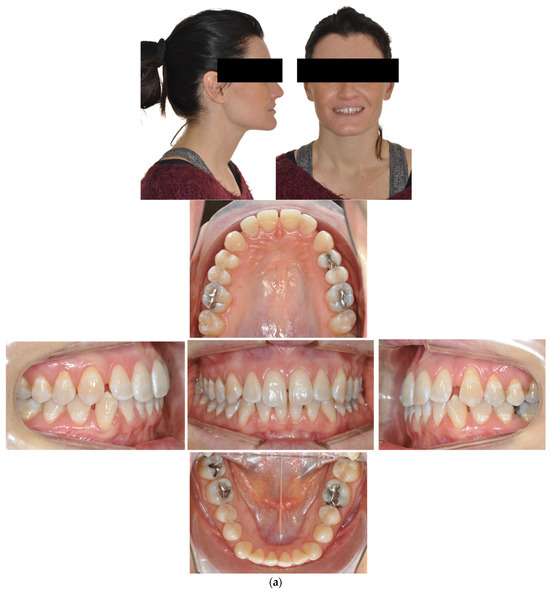

- Case 1: Class II division 2 with deep bite

4.1. Case 1: Class II Division 2 with a Deep Bite